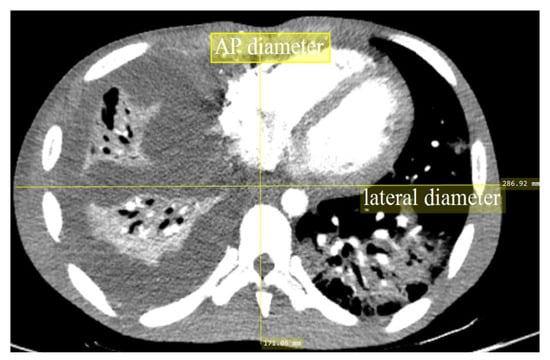

2.4. Image Quality Evaluation

| AP body length (cm) * | 19.79 ± 2.61 | 20.81 ± 2.52 | 23.38 ± 3.58 | 23.36 ± 2.47 |

| AP Body Length (cm) * | 14–19 | 19–24 | 24–31 | p-Value |

|---|---|---|---|---|

| Dose Reference Level (mGy) | 6.13 | 8.35 | 21.40 | <0.001 |

| Dose Reference Range (mGy) | 4.73–7.55 | 6.13–11.50 | 13.70–25.20 | n.a. |

| Noise Reference Level (HU) | 23.78 | 24.26 | 23.97 | 0.703 |

| Noise Reference Range (HU) | 20.49–28.18 | 21.80–27.50 | 19.02–28.60 | n.a. |